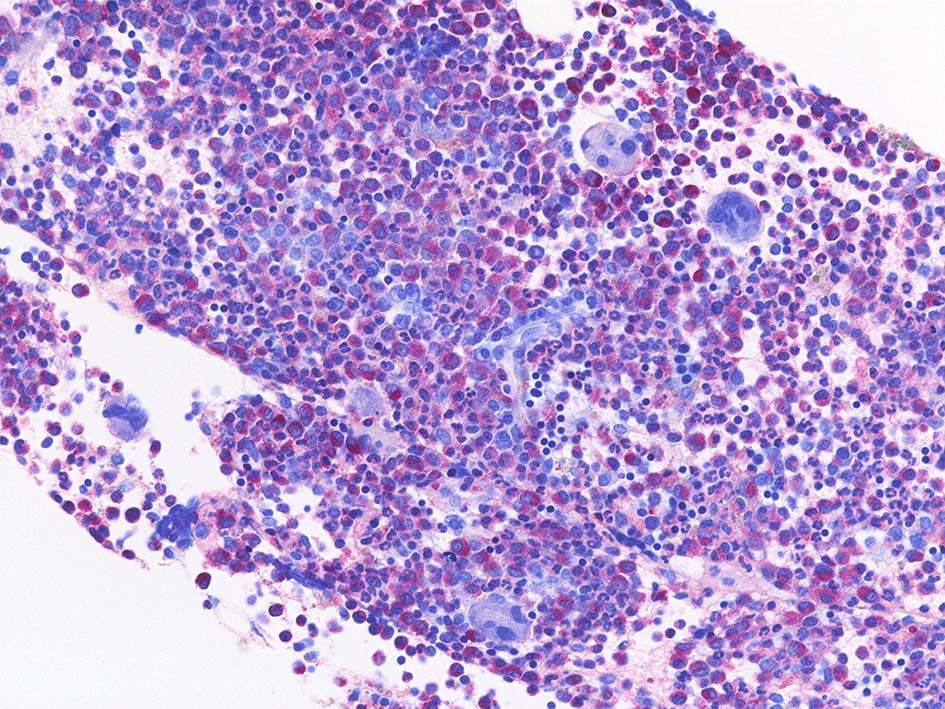

Naphtohl-ASD-CAE Fig.01

Fig.01: hypercellular marrow. ASDで赤染する細胞の増加=granulopoietic hyperplasiaがある.

Fig.02: 幼若な顆粒球が増加している. 赤芽球は散在しており血島は不明瞭である. 過形成髄なのにFig.02に成熟大型巨核球はみられない.

Fig.03: granulopoietic hyperplasia. 成熟顆粒球の増加もある.

Naphtohl-ASD-CAE